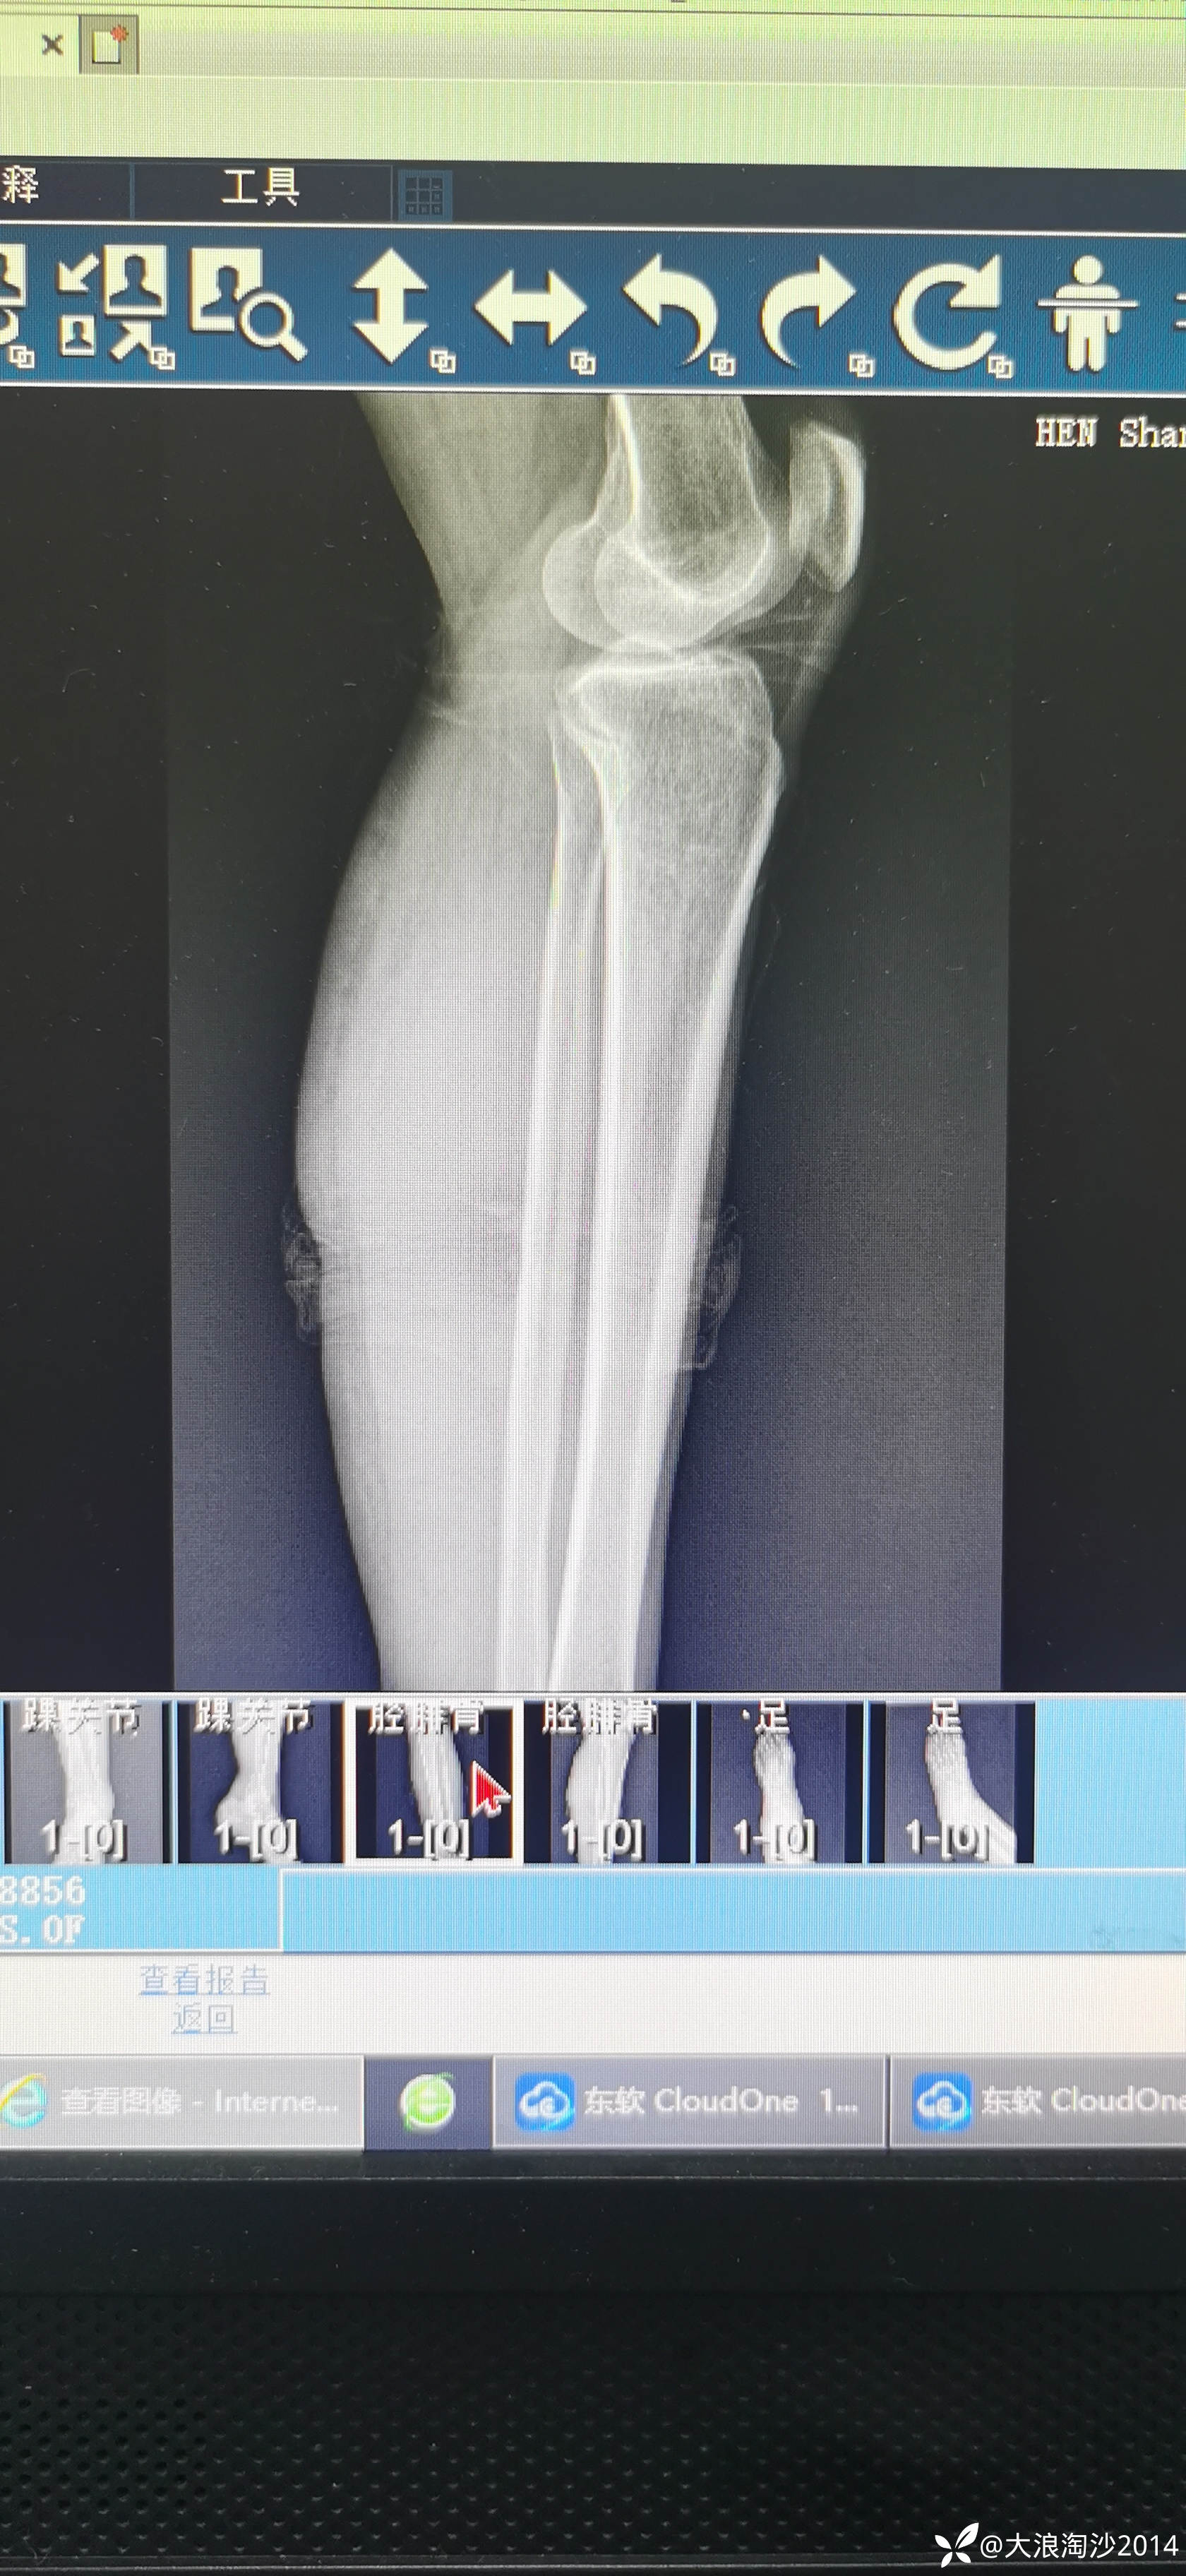

一65岁女性患者,偏瘦,体重75斤,车祸外伤致左胫腓骨远端骨折,入院后消肿后,病人可以用皮包骨头形容,考虑胫骨远折端不适合用内侧插板(mippo技术),病人太瘦,如取两个切口分别处理胫腓骨,切口容易出现问题,因此采用前外侧一个切口处理胫腓骨远端骨折(片子顺序上传有点乱)